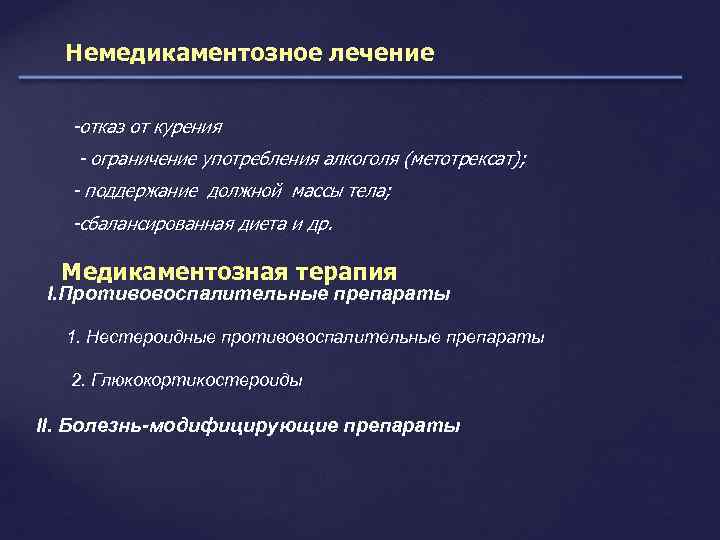

Немедикаментозное лечение -отказ от курения - ограничение употребления алкоголя (метотрексат); - поддержание должной массы тела; -сбалансированная диета и др. Медикаментозная терапия I. Противовоспалительные препараты 1. Нестероидные противовоспалительные препараты 2. Глюкокортикостероиды II. Болезнь-модифицирующие препараты

Немедикаментозное лечение -отказ от курения - ограничение употребления алкоголя (метотрексат); - поддержание должной массы тела; -сбалансированная диета и др. Медикаментозная терапия I. Противовоспалительные препараты 1. Нестероидные противовоспалительные препараты 2. Глюкокортикостероиды II. Болезнь-модифицирующие препараты